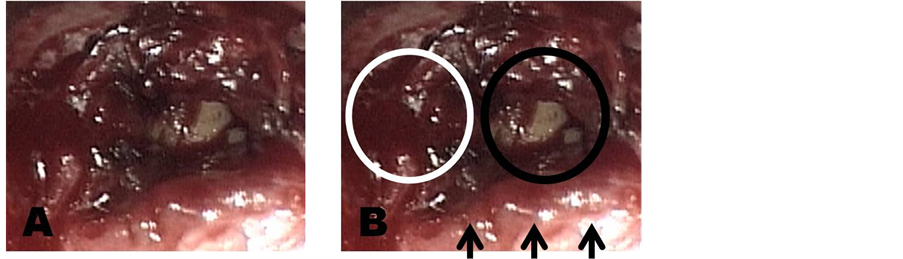

All the patients were operated through a transsphenoidal microsurgical approach, endoscope-assisted from 2000. Operation was performed through one nostril, by a submucosal access to the anterior wall of sphenoidal plane. Then, after opening of the sella turcica, dura mater was exposed (Figure 2) and then opened; in all patients a clear microadenoma was exposed and removed by dissection and aspiration, achieving a micro surgical cave into the context of the pituitary gland which was spared (Figure 3). In all cases, the limits of the surgical cave were coagulated by dedicated bipolar. Starting from 2003, in all patients affected by secreting microadenoma without evidence of intraoperative CSF leak, we used to apply intraoperative absolute alcohol at the end of tumor removal. So that in patients of group one, all operated from 2003 through to 2008, intraoperative application of absolute alcohol was performed, as reported: at the end of microadenoma removal, in all cases a surgical cave was evident, and a micro-surgical patty (0.5 × 0.5 cm) soaked in absolute alcohol was applied into the micro-surgical cave and kept in situ for about 2 minutes (Figure 4); this operation was repeated 3 - 4 times. In patients of group two, operated from 1998 through to 2003 and in 2 cases in 2007, intraoperative absolute alcohol was not applied. In the last 2 cases of group two, intraoperative application of absolute alcohol was not performed because of intraoperative CSF leak, to don’t run the risks of alcohol diffusion into the subarachnoid space.

Figure 2. Microsurgical view of exposition of pituitary and peritumoral dura mater.

Figure 3. (A) Microsurgical view of the operative field after removal of microadenoma. (B) The white circle indicates the left side of the pituitary gland; the black circle indicates the operative microsurgical field in the right portion of the pituitary gland; the short black arrows indicate the superior part of the dura mater over the suprasellar cistern.